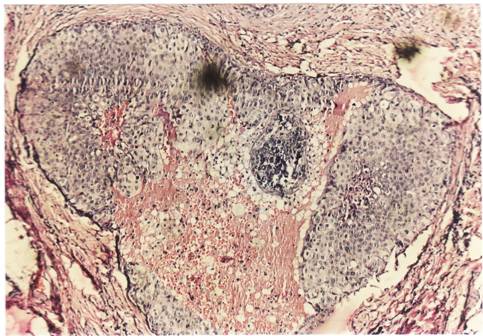

Criterii microscopice de diagnosticare a cancerului mamar

Pentru examenul histopatologic piesele de mamectomie sunt prelucrate prin imparafinare si colorate cu Hematoxilina-Eozina sau, pentru observarea mai buna a tesutului conjunctiv, cu Van Gieson.

Colorarea se realizeaza pentru observarea difertiata a structurilor celulare (colorantul adera selectiv la structurile celulare, colorandu-le diferit). Hematoxilin-eozina contine hematoxilina si eozina (colorant acid anionic). Colorantul se oxideaza la aer in timp indelungat sau chimic, cu iodura de sodiu. Colorantul determina culoarea roz a citoplasmei celulare, nucleul bazofil (albastru-violet), heterocromatina se coloreaza intens, dar nu si invelisul nuclear, nucleolii apar foarte colorati si in citoplasma se observa granule albastru- violacee, ce sunt ribozomii, care contin ARN.

Pe preparate colorate, la microscopul optic se observa urmatoarele imagini :